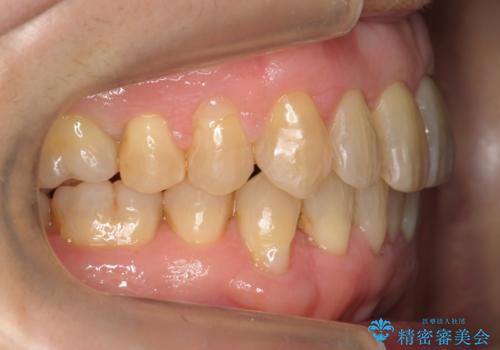

- 前歯のがたつきを主訴に来院。

右下の犬歯が歯ぐきが痩せて、歯肉退縮しておりそれを抜歯しました。

上の前歯はIPRを行なっています。

右下の犬歯の1本抜歯で最小限の抜歯で並べることができました。

奥歯も上下交互になるようにかみ合わせることができました。